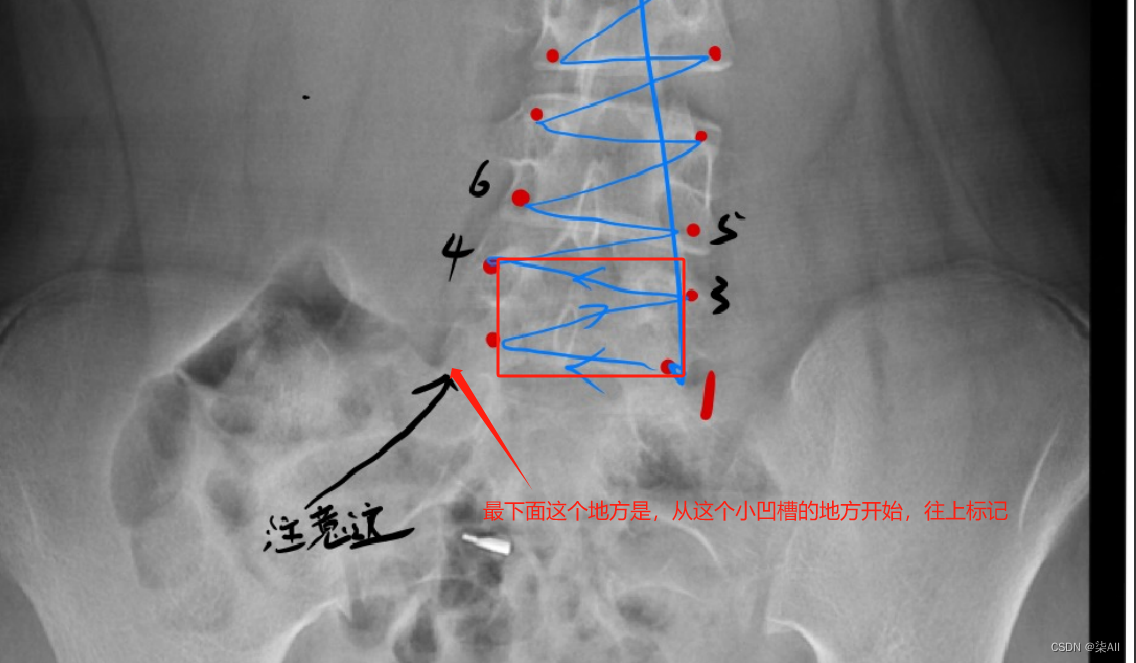

2、开始标注(以冠状位为例,其他方位是一样的操作,视频教程)

冠状位关键点标注教程

5、标注结果注意

(0) 最后一个椎体看不清的话,最后一个肋骨连接的就是胸12 也就是T 12 ,下面那个就是L1(腰椎1),往下数五个就是 最后一个腰椎

(1)标注的椎体应该近似是一个矩形,而不是梯形 如下图

(2)标注的时候关键点 不要(X)标记的太靠 边 ,但是 也不要往内收的太厉害

下图这个就不太行

(3)像这种椎骨不要变化太大,一般都是底下的椎骨大一些,往上逐渐减少,就因为看不清,所以得这样表

还是有很多问题的,这种计算cobb角肯定有问题,最后一个椎骨看不清,那画的线就与上一个椎骨平行,尽量平行标,要不然后面自动生成cobb角,误差很大,这样肯定不行,注意一下,认真一些,要不然得返修几次,不如好好弄,还节省时间